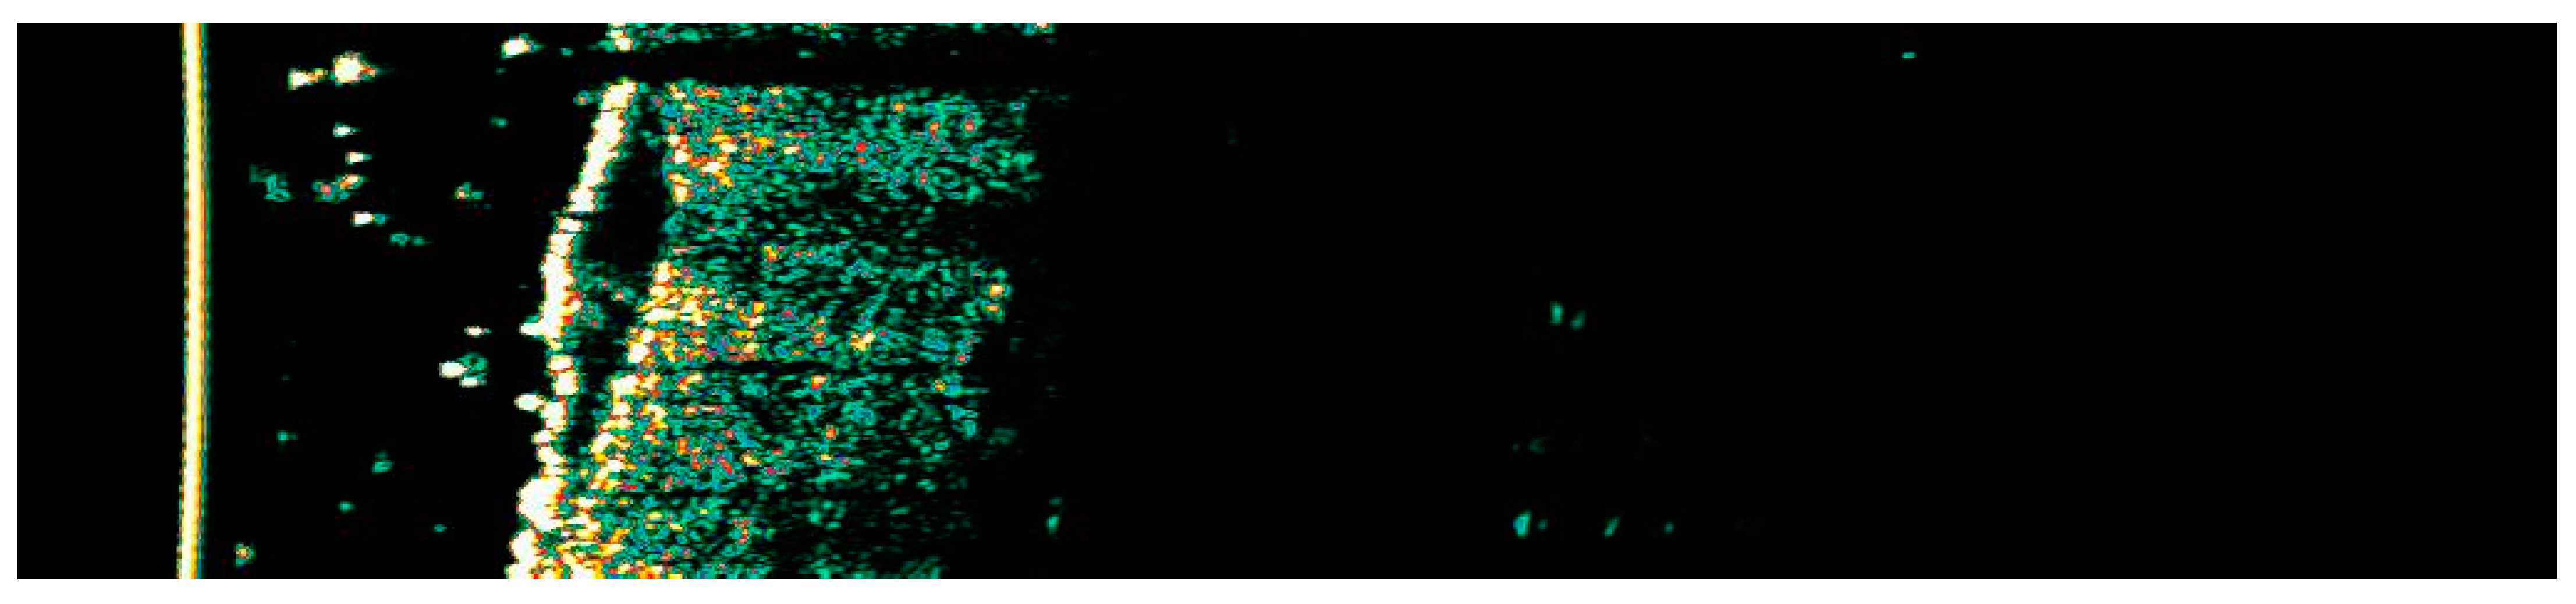

Figure 5. Ultrasonographic image of BCC on the temple.

The Figure 1, Figure 2, Figure 3, Figure 4, Figure 5, Figure 6, Figure 7, Figure 8, Figure 9, Figure 10, Figure 11, Figure 12, Figure 13, Figure 14, Figure 15, Figure 16, Figure 17, Figure 18, Figure 19, Figure 20, Figure 21, Figure 22, Figure 23, Figure 24, Figure 25, Figure 26, Figure 27 and Figure 28 alternately display ultrasound images and dermoscopic observations of the treated basal cell carcinoma (BCC) lesions. These images provide a visual representation of the textural and vascular changes observed during different stages of the healing process post-HIFU treatment, demonstrating the involution from immediate tissue responses to the long-term healing and remodeling of the skin.